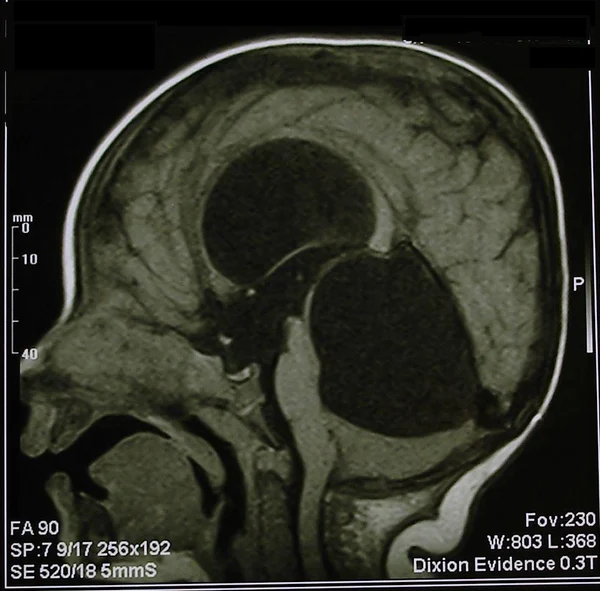

кисты, аномалии Денди-Уокера и др.Операции при внутричерепных кистах. В основном встречаются арахноидальные кисты различных локализаций и кисты сосудистых сплетений боковых желудочков. Пациентам с врождёнными кистами операции проводятся в следующих ситуациях: увеличении объема кисты в динамике, наличии клинических проявлений, компрессии и дислокации мозговых структур, наличии окклюзии ликворных путей. Нами используются 2 способа хирургического лечения кист: эндоскопическая перфорация стенок кист и открытая резекция кист. Открытая резекция кист проводится при ретроцеребеллярных арахноидальных кистах (рис. 2), при арахноидальных кистах межполушарной щели при отсутствии непосредственного контакта их стенок со стенками расширенных желудочков головного мозга и повторного увеличения кист средней черепной ямки после эндоскопической кисто-цистерностомии. Техника операции заключается в проведение краниотомии и максимальном иссечении стенок кист с созданием широкого сообщения кист с субарахноидальным пространством. Эндоскопические операции проводятся при арахноидальных кистах межножковой и пинеальной цистерн, арахноидальных кистах межполушарной щели при тесном контакте их стенок со стенками расширенной желудочковой системы (рис. 3), первично при арахноидальных кистах средней черепной ямки, а также при кистах сосудистых сплетений боковых желудочков. При арахноидальных кистах межножковой цистерны эндоскопически проводится перфорация стенок кисты, сообщая ее с просветом III желудочка и межножковой цистерной – эндоскопическая вентрикуло-кисто-цистерностомия (рис. 4). При арахноидальных кистах пинеальной цистерны проводится перфорация кисты в передне-верхних её отделах с созданием сообщения полости кисты с просветом III желудочка – эндоскопическая кисто-вентрикулостомия. С целью предотвращения облитерации сформированного отверстия иногда в полость кисты под контролем эндоскопа вводится стент перфорированный на протяжении (рис. 5, 6). Эндоскопическая кисто-цистерностомия выполняется при арахноидальных кистах средней черепной ямки. При этом создается широкое сообщение кисты с базальными цистернами. При кистах сосудистых сплетений боковых желудочков проводится их вскрытие в просвет боковых желудочков – эндоскопическая кисто-вентрикулостомия. При множественных кистах проводится их хирургическое сообщение между собой – интеркистосмия